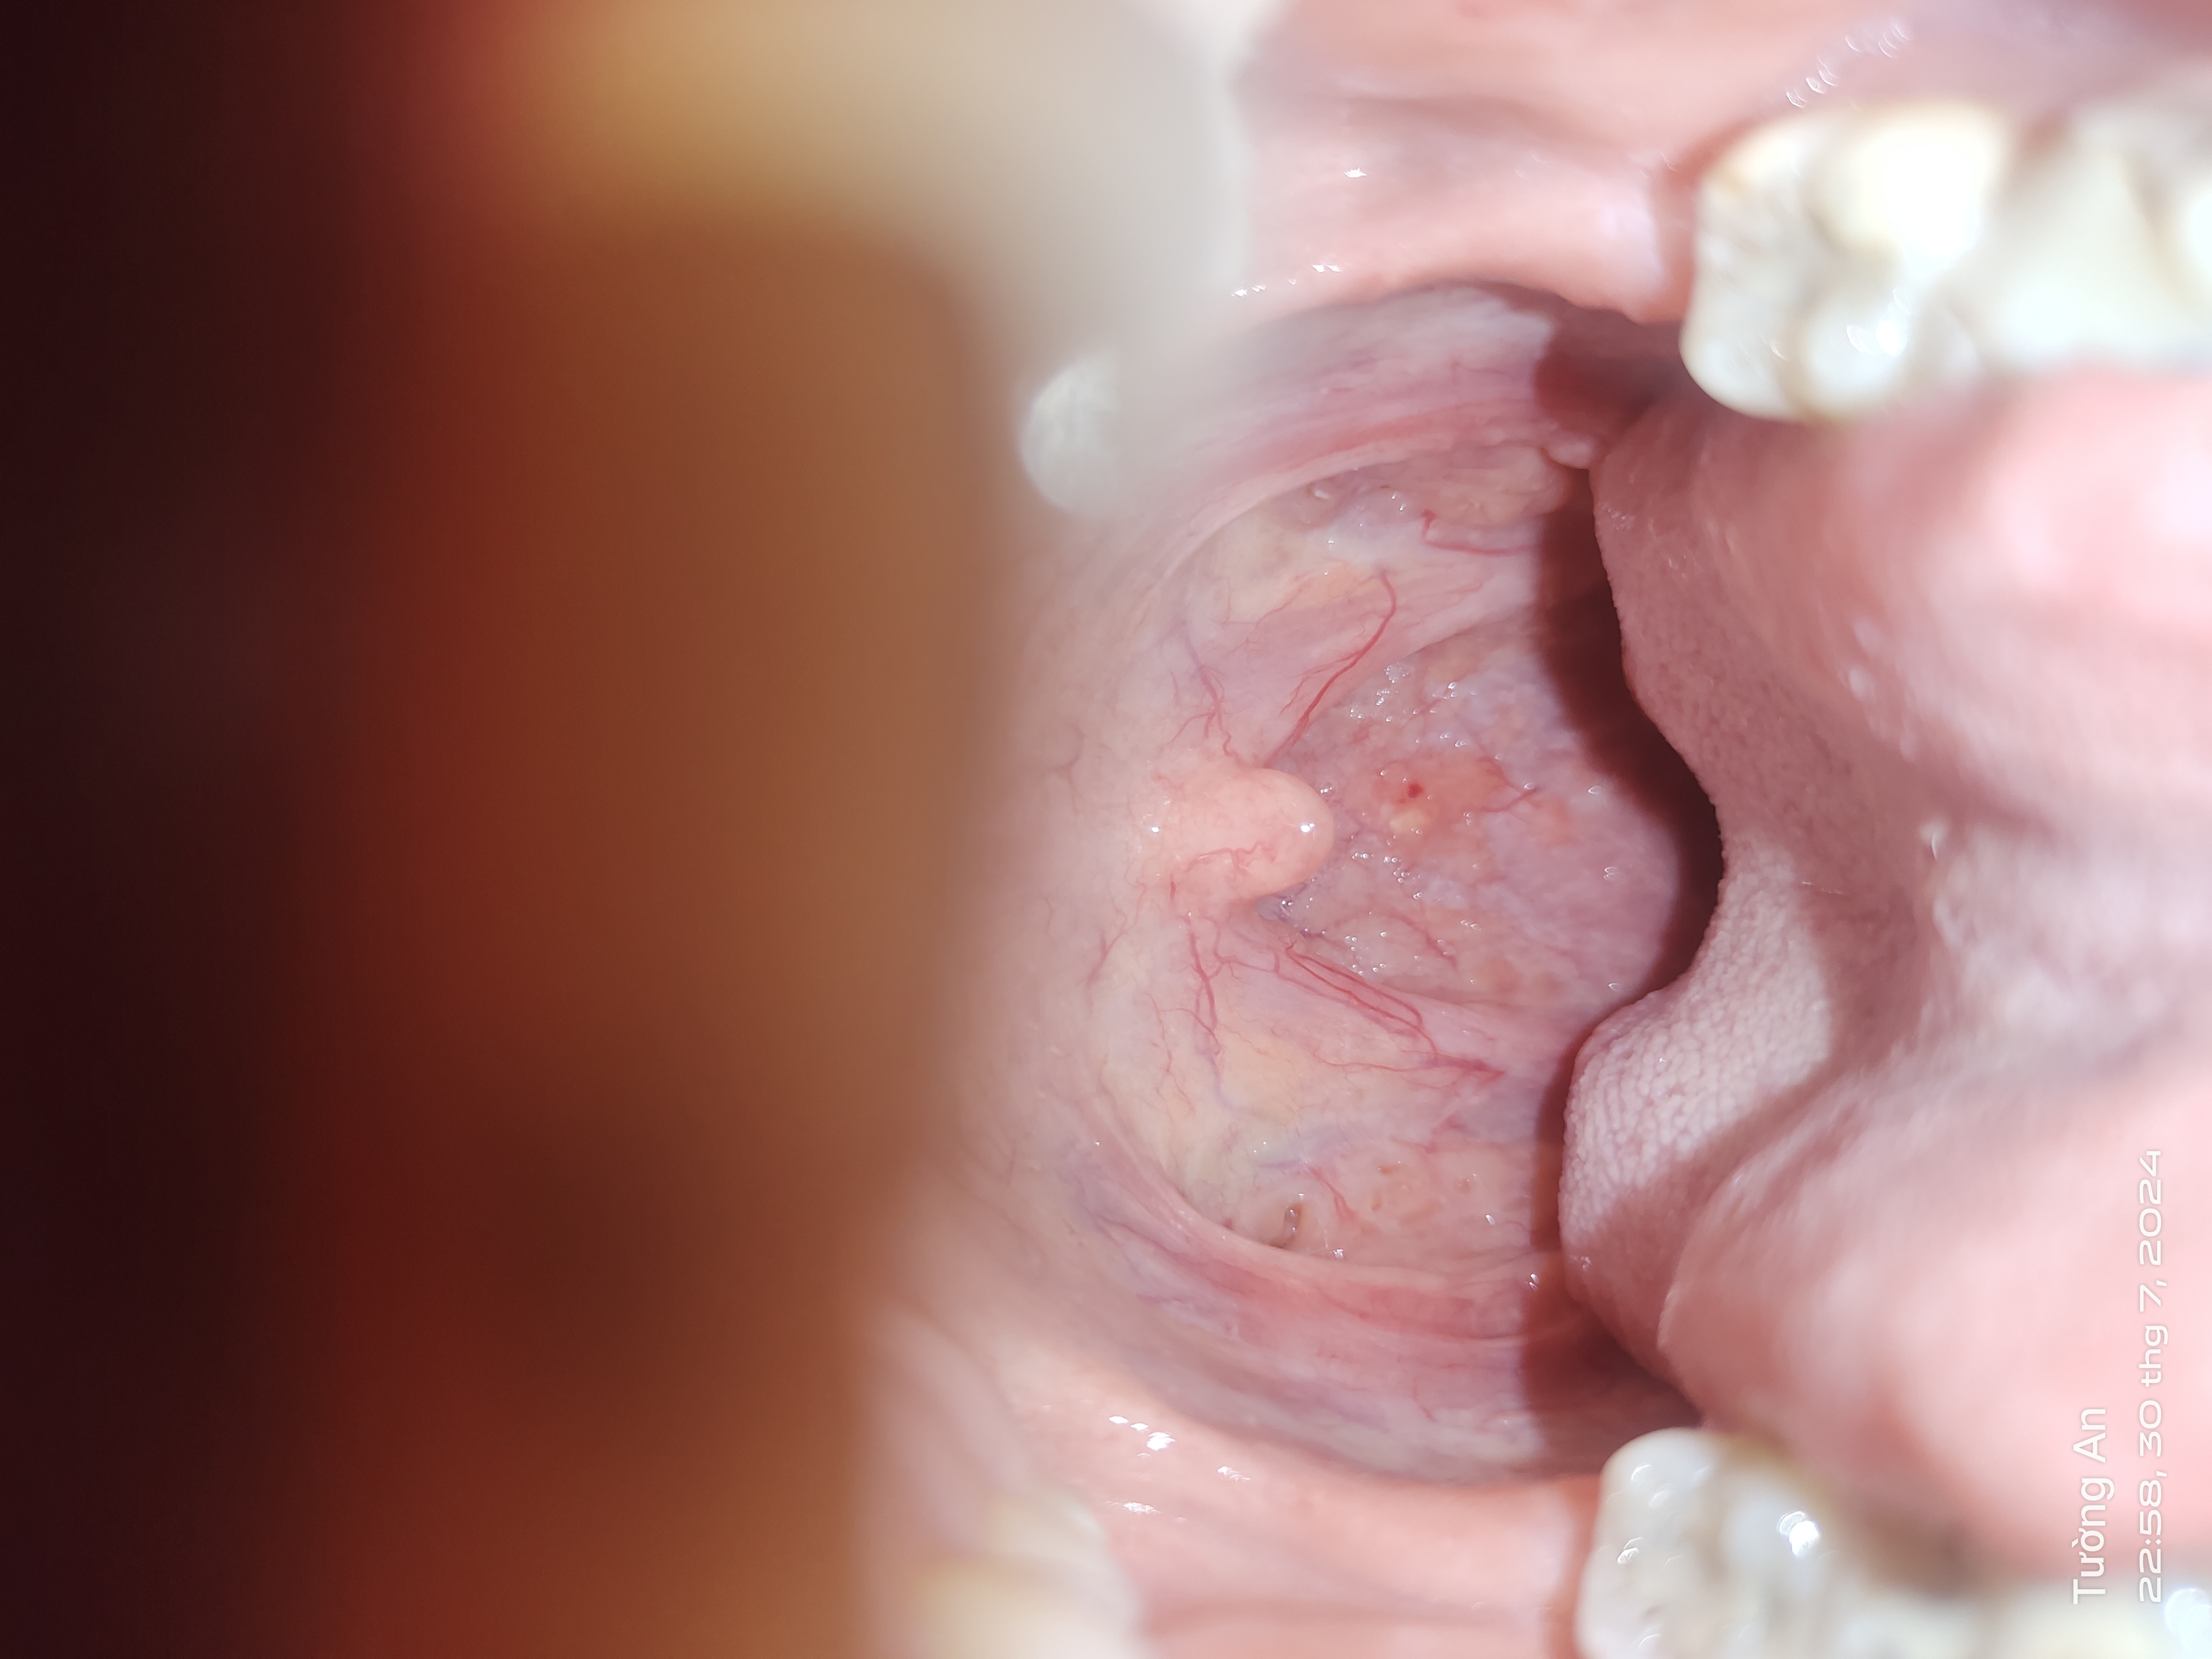

Trong thành cổ họng ngay chổ chấm đỏ có màu vàng (không phải nốt mà nó phẳng với bề mặt da) vậy cổ họng có bất thường không bs

Hình ảnh viêm họng hạt. Các hạt này các hạt lympho lành tính